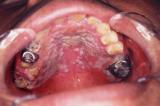

舌や頬などの口腔内の粘膜に白い苔のようなものが付着する病気に口腔カンジダ症があります。

舌が痛くなったり、違和感を感じたり、味覚がおかしくなったりすることもあります。

唇の両端が赤く腫れ上がったり、白いただれができたりする場合もあります。

カンジダ症の原因となるカンジダ菌は元々、人間の体の中に存在しているカビの仲間です。                                            体の免疫力が低下したときにカンジダ症として症状が出てきます。

口腔カンジダ症は特にその性質が強く、ステロイド薬や抗生剤を内服している患者や、高齢者、乳幼児によく見られます。

乳幼児は不潔な乳首に原因があることがあります。